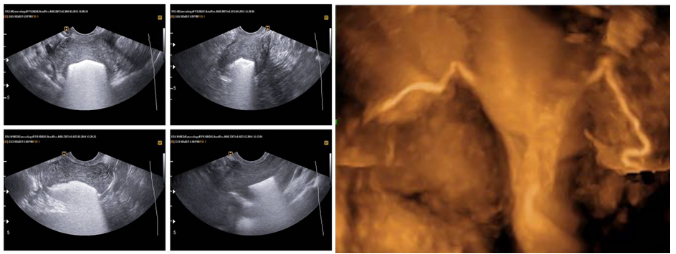

Pianka ExEm Foam umożliwia łatwą i bardzo skuteczną ocenę drożności jajowodów podczas wykonywania procedury HyCoSy.

Zestaw został specjalnie opracowany do tworzenia pianki z mikrobąbelkami, która wprowadzona poprzez jamę macicy do jajowodów powoduje idealne rozszerzenie ich ścian.

Stosując ExEm®Foam otrzymujemy wysokiej jakości obraz USG.

- Umożliwia uzyskanie jasnej wizualizacji konturu jajowodów